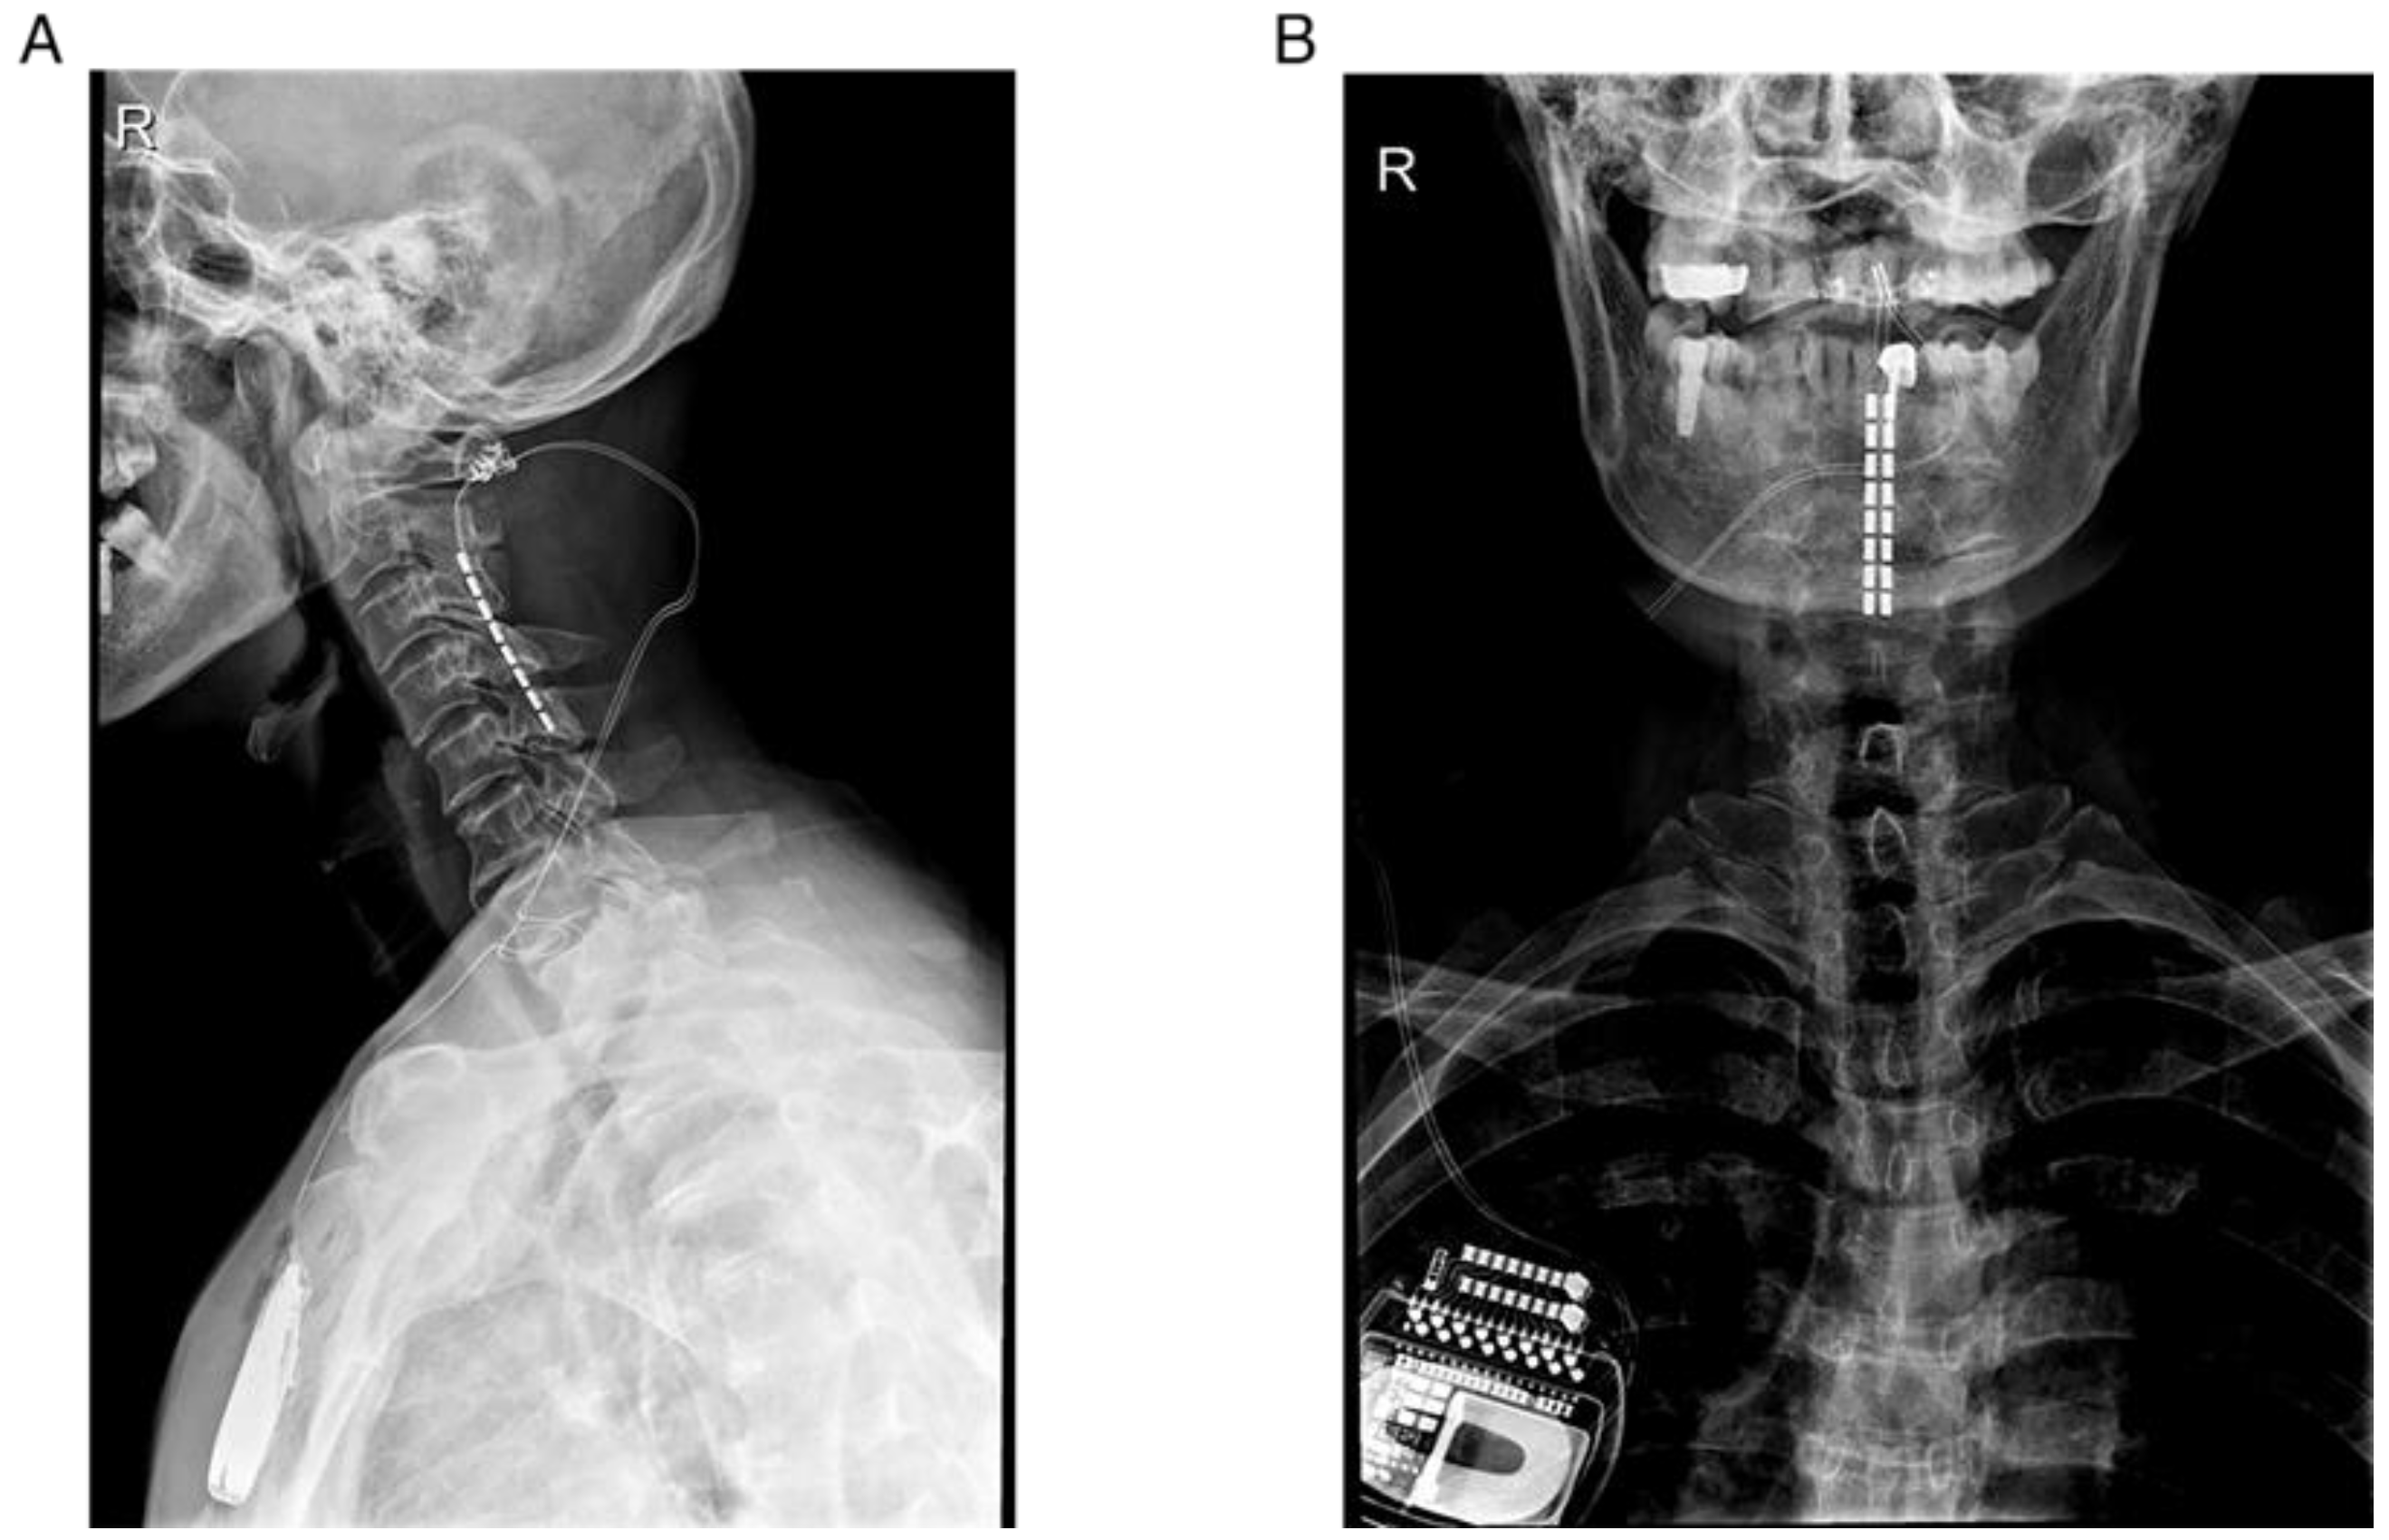

2.3. Surgical Procedure

| No.1 | 53 | M | 1164.25 | PD | 13 | Yes | C2–C5 | 6 |

| No.2 | 75 | M | 550 | PD | 7 | No | C2–C5 | 6 |

| No.3 | 63 | M | 900 | PD | 4 | No | C2–C5 | 6 |

| No.4 | 60 | F | 600 | MSA-P | 6 | No | C2–C5 | 6 |

| No.5 | 61 | F | 500 | MSA-P | 6 | No | C2–C5 | 6 |

| No.6 | 58 | F | 575 | MSA-P | 4 | Yes | C2–C5 | 6 |

| No.7 | 54 | M | 300 | MSA-P | 1 | No | C2–C5 | 7 |

| No.8 | 67 | F | (-) | MSA-P | 3 | No | C2–C5 | 7 |